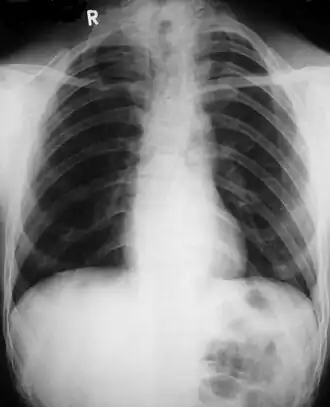

![]() Дефекты ключиц и сужающаяся грудная клетка | |

- Недоразвитие или отсутствие одной или обеих ключиц. При отсутствии или недоразвитии ключицы плечевой пояс резко сужен, надплечья покаты и опущены. Отмечается избыточная подвижность в плечевых суставах, возможно даже соприкоснуться плечами спереди грудины.

Диагностика ключично-черепного дизостоза основана на клинических симптомах и рентгенологических исследованиях, которые включают изображения черепа, грудной клетки, таза и рук. Главный рентгенологический симптом — дефекты ключиц. Обычно отсутствует наружный (акромиальный) конец ключицы, в то время как внутренний (грудинный) конец присутствует. Но иногда ключица состоит из двух фрагментов. Полное отсутствие ключицы встречается редко.